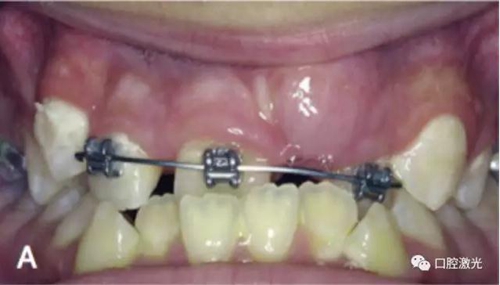

治療前

激光牙齦切割后即刻

在近似理想位置粘接托槽

6周后效果